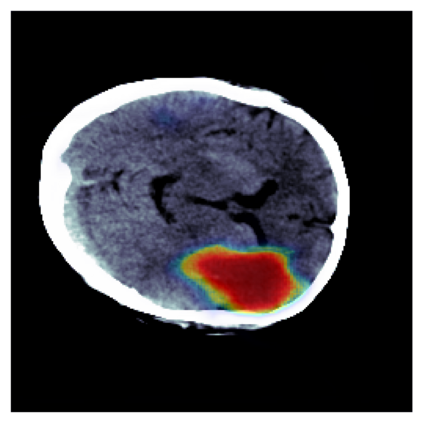

The sigmoid activation is the standard output activation function in binary classification and segmentation with neural networks. Still, there exist a variety of other potential output activation functions, which may lead to improved results in medical image segmentation. In this work, we consider how the asymptotic behavior of different output activation and loss functions affects the prediction probabilities and the corresponding segmentation errors. For cross entropy, we show that a faster rate of change of the activation function correlates with better predictions, while a slower rate of change can improve the calibration of probabilities. For dice loss, we found that the arctangent activation function is superior to the sigmoid function. Furthermore, we provide a test space for arbitrary output activation functions in the area of medical image segmentation. We tested seven activation functions in combination with three loss functions on four different medical image segmentation tasks to provide a classification of which function is best suited in this application scenario.